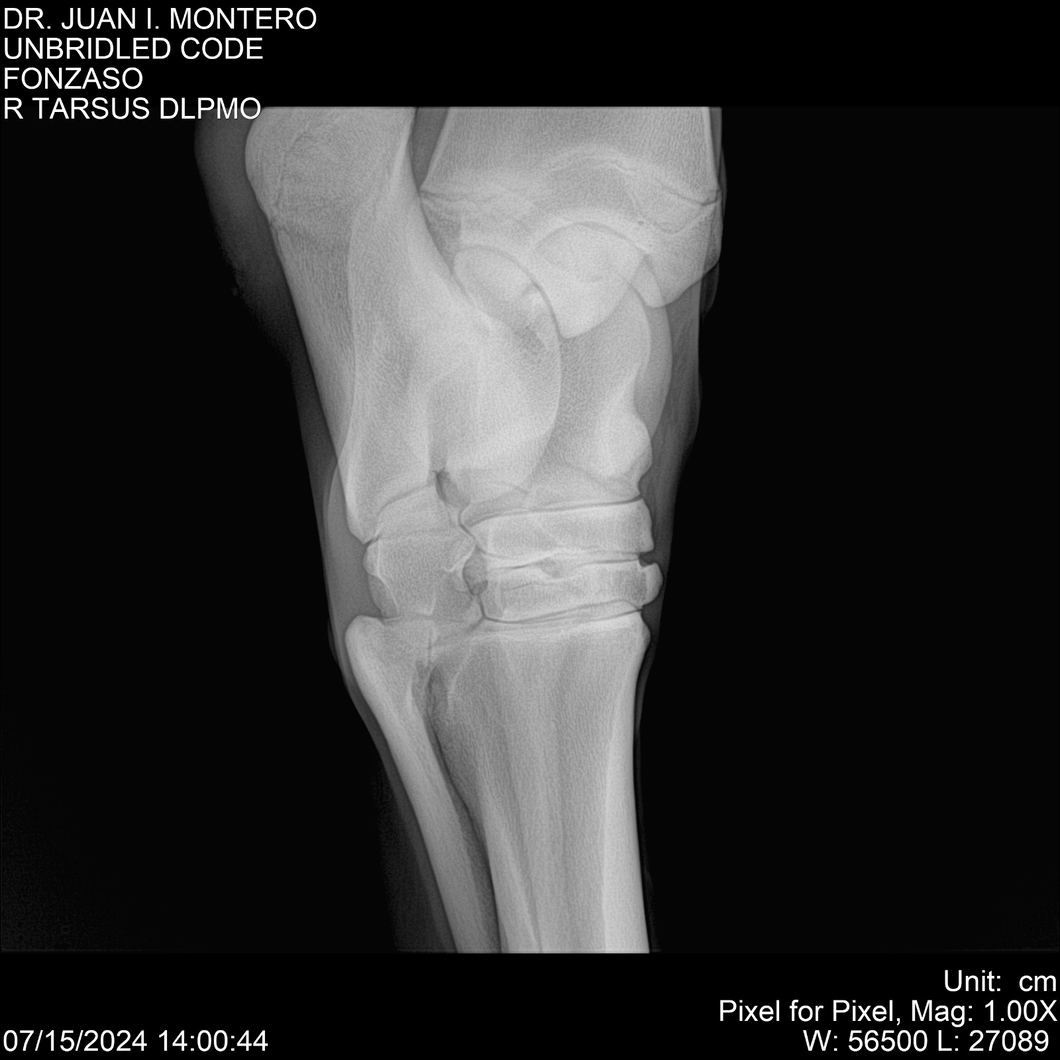

• Empresa: Abelenda N. R., Walter Hugo